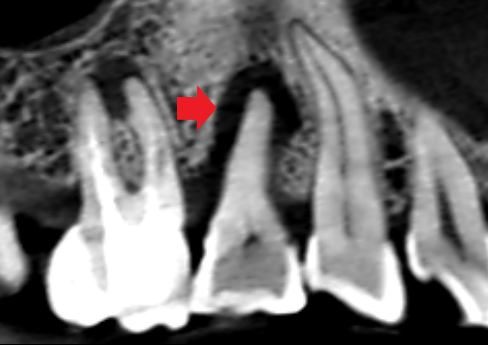

マイクロスコープ歯周再生療法を行ったケース。歯の周囲の骨が回復している。